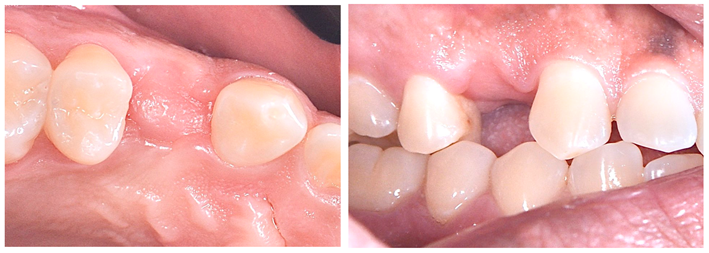

Constatada a perfeita osteointegração, realizou-se a reabertura do implante e instalação do dente provisório (Figuras 12 e 13) visando o condicionamento gengival para formação e maturação correta do perfil gengival previamente à confecção da coroa definitiva.